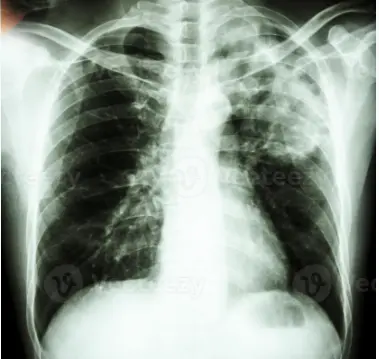

La Consellería de Sanidad conmemora este 24 de marzo el Día Mundial de la Tuberculosis, cuyo lema es "Sí, podemos poner fin a la tuberculosis", reiterando su compromiso de continuar con los esfuerzos y actuar en consonancia con la estrategia "Fin a la tuberculosis", de la Organización Mundial de la Salud, que tiene por objetivo reducir el incidente de la tuberculosis un 80% en el año 2030 con respeto al 2015 para, posteriormente, eliminar esta enfermedad en el 2050.

El desarrollo del Programa gallego de prevención y control de la tuberculosis de la Dirección General de Salud Pública de la Consellería de Sanidad, permite realizar el diagnóstico el más rápido posible y poner a todos los enfermos bajo tratamiento para reducir este riesgo. Al mismo tiempo, se realiza el estudio a todas las personas que estuvieron en contacto con un caso de tuberculosis contagiosa y se ofrece tratamiento a aquellos que están infectados, evitando que desarrollen la enfermedad en un futuro.

La localización más frecuente fue la pulmonar (62,0%) y de ellos el 39,3% fueron casos bacilíferos (muy contagiosos).